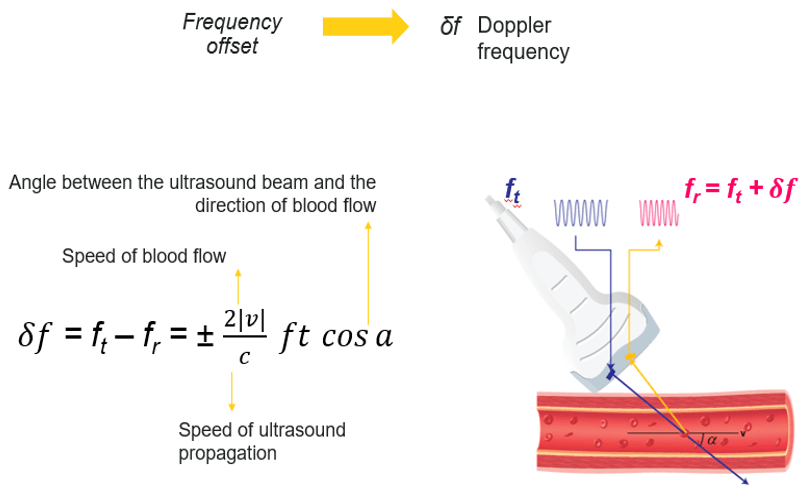

The Doppler equation shows the relationship between the transmitted Doppler shifted signal (Ft) and the blood flow velocity (V): V = c/(2ft cos a).δf, where the following represent: δf is the Doppler-shifted signal, Ft is the transmitted Doppler frequency, c is the propagation speed of ultrasound in soft tissue, V is the velocity of the moving blood, and a is the angle between the Doppler ultrasound beam and the direction of blood flow.

The number 2 is a constant indicating that the Doppler beam must travel to the moving target and then back to the transducer.

Effect of Angle

Note that the Doppler frequency also varies according to the angle alpha. The value of cosα varies with the angle from 0 to 1. When α = 0°, cosα = 1 and when α = 90°, cosα = 0.

For a constant flow velocity (V), the maximum value of cosα and therefore the highest value of the Doppler-shifted signal (δf) is at an angle of 0°. This corresponds to a Doppler beam which is parallel with the vessel, which can rarely be achieved in practice.

Theoretically, when α = 90° this means the blood flow is perpendicular to the Doppler beam, cosα = 0 and no Doppler-shifted signals will register.

In practice, when measuring the blood flow, a Doppler beam angle between 30 and 60° ensures reliable Doppler-shifted signals. Avoid using angles greater than 60 degrees and remember no Doppler-shifted signals are generated at 90 degrees. The smaller the angle, the more reliable is the recorded Doppler speed.